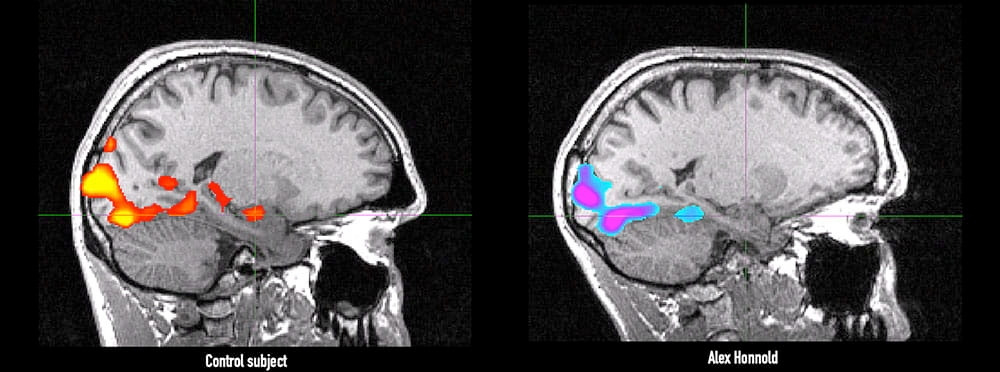

암벽 가장자리에서 로프 없이 서 있는 사람의 심정은 어떨까요? 대부분은 아찔한 공포에 심장이 요동칠 것입니다. 그러나 세계적인 프리솔로 등반가 알렉스 호놀드는 달랐습니다. 과학자들이 그의 뇌를 fMRI로 들여다본 결과, 일반인에게선 번쩍이는 공포의 중심인 편도체가 호놀드의 뇌에서는 놀랄 만큼 잠잠했던 것입니다.

2016년, 다큐멘터리 Free Solo의 촬영 중 한 과학 저널리스트의 제안으로 알렉스 호놀드는 사우스캐롤라이나 의대(MUSC)의 뇌과학 연구실을 찾았습니다. 편도체(amygdala)의 반응을 살펴보는 실험에 참여한 것이지요.

편도체는 뇌 측두엽 깊숙이 위치한 아몬드 모양의 신경핵으로, 전통적으로 “두려움 감지기”로 알려져 있습니다. 연구진은 호놀드에게 일상적인 풍경 사진부터 끔찍한 사고 장면이나 뱀·거미 같은 공포 유발 이미지까지 45분간 연속해서 보여주며 뇌 활동을 측정했습니다.

일반 참가자라면 불쾌감을 느끼고 은근한 스트레스를 받는 시험이었지만, 호놀드는 MRI 스캐너에서 나와 한마디 했습니다. “뭐죠? 아무 느낌 없는데요?” 연구를 이끈 제인 조지프 박사는 놀랄 수밖에 없었습니다. 대조군으로 참여한 같은 또래의 평범한 클라이머조차 “별 느낌 없다”고 말하면서도 뇌 편도체는 선명히 빛을 냈건만, 호놀드의 편도체는 완전히 관성적인 – 즉 “어떠한 활동도 보이지 않을” 정도로 무반응이었던 것입니다.

그의 뇌 스캔 화면에서 공포로 유명한 이 편도체 영역은 회색으로 잠잠하게 유지되었습니다. 마치 호놀드에게는 불안과 공포를 호출하는 뇌의 경보 시스템 자체가 꺼져 있는 것처럼 보였지요.